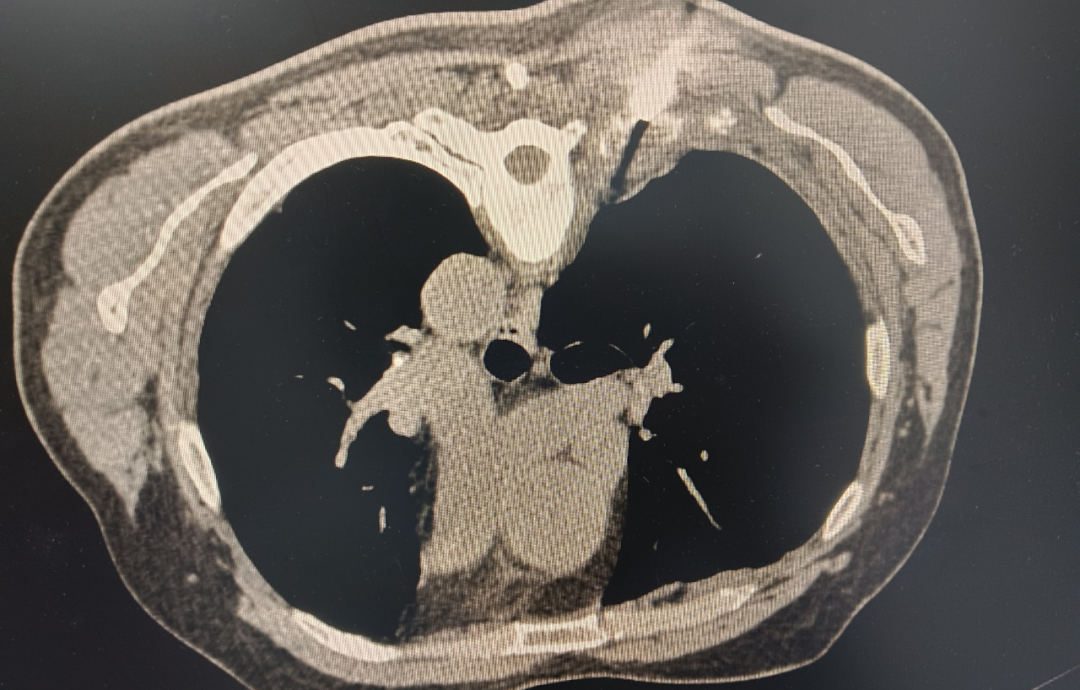

近期我院肿瘤科收住一例疑是前列腺癌并全身多发骨转移的患者,经CT引导下肋骨转移瘤穿刺活检术,术后病理+免疫组化检查确诊:前列腺癌并骨转移,目前患者已得到及时规范治疗。 术中图像 经皮穿刺活检术是一种微创检查技术,通过细针在CT或B超引导下经皮肤穿刺至病变部位获取组织或细胞样本,用于病理诊断,帮助明确病变性质(如良恶性)、指导治疗方案制定。 什么情况下需要做这个检查? 1.肺部病变:肺内孤立性结节或肿块、多发结节、肺 实变、磨玻璃病变等,需明确病变性质。 2.其他部位病变:胸膜、纵隔、肋骨、胸骨、胸椎等胸壁病变,或肝脏、肾脏、甲状腺、淋巴结等其他器官的占位性病变,当其他检查无法明确诊断时。 3.已知恶性病变:需明确组织学类型、分子病理学类型,或疾病进展、复发后需再评估病理特征。 哪些人不适合做这个检查? 1.严重凝血功能障碍或出血倾向未纠正。 2.严重肺气肿、肺动脉高压、肺血管性病变(如动脉瘤、动静脉畸形)。 3.穿刺路径上有感染病灶、肺大疱或紧邻心脏、大血管、主支气管的病变。 4.不能配合检查(如无法控制的剧烈咳嗽、不能平卧)。 5.严重心肺功能不全、未控制的高血压等。 检查前需要做什么准备? 1.完善检查:包括血常规、凝血功能、肝肾功能、心 电图、肺功能等,必要时进行增强CT或PET-CT检查。 2.停用抗凝药物:如阿司匹林、氯吡格雷、华法林等,一般需提前3-7天停用,具体遵医瞩。 3.屏气训练:练习平静呼吸后屏气5秒,以减少穿刺时呼吸运动的影响。 4.心理准备:了解检查过程和注意事项,缓解紧张情绪。 术后需要注意什么? 1.休息与活动:术后需卧床休息24小时,避免剧烈咳嗽、运动及用力排便,防止穿刺部位出血或气胸加重。 2.观察症状:注意有无胸痛、呼吸困难、咯血、出汗、心悸等异常,如有需及时告知医生。 3.伤口护理:穿刺部位3天内避免沾水,保持干燥,防止感染。 4.饮食:术后可进食温凉、清淡、易消化的食物,避免辛辣、刺激性食物。 可能出现的风险 1.气胸:最常见,发生率约10%-30%,多在术后24小时内出现,少量气胸可自行吸收,大量气胸需胸腔闭式引流。 2.出血:如痰中带血或少量咯血较常见,一般无需特殊处理,大咯血需及时就医。 3.空气栓塞:罕见但严重,可能危及生命。 4.肿瘤针道种植:发生率极低(约0.012%-0.061%),现代技术已进一步降低风险。 穿刺结果意味着什么? 1.阳性结果 找到癌细胞,明确了诊断。 2. 阴性结果 未发现癌细胞,但不能完全排除恶性可能。 3. 不确定结果 可能需要进一步检查或手术。 值得注意的是,穿刺活检阴性不等于100%排除恶性肿瘤,医生会结合临床情况综合判断。 健康咨询 咨询电话:0775—3372360 门诊部地址:桂平市中医医院2号楼4楼 住院部地址:桂平市中医医院1号楼5楼 |